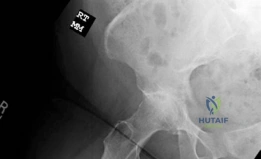

Standardized radiographic evaluation is the cornerstone of diagnosing and templating for total hip arthroplasty. A complete hip series was obtained, including a weight-bearing anteroposterior (AP) view of the pelvis, an AP view of the right hip, and a lateral view of the right hip.

The preoperative AP radiograph of the pelvis demonstrates end-stage, Kellgren-Lawrence Grade IV osteoarthritis of the right hip. There is complete obliteration of the superior and axial articular joint space, indicating full-thickness chondral loss.

Focusing on the AP view of the right hip, profound subchondral sclerosis is visible on both the acetabular and femoral sides, representing Wolff's law in action as the bone hypertrophies in response to abnormal, unbuffered mechanical stress. Large, marginal osteophytes are present at the lateral acetabular rim and the femoral head-neck junction, contributing to the patient's mechanical block to motion. Subchondral cystic changes (geodes) are also noted within the acetabular roof, resulting from the intrusion of pressurized synovial fluid through microfractures in the denuded subchondral bone plate.

The preoperative lateral radiographs confirm the extensive circumferential nature of the osteophytic rim and the posterior loss of joint space. The femoral head has lost its normal spherical geometry, taking on a flattened, "mushroom" appearance due to the advanced degenerative remodeling. The proximal femoral diaphysis appears to have a robust cortical thickness, consistent with a Dorr Type A or B bone morphology, which is highly favorable for an uncemented, diaphyseal-engaging femoral stem.